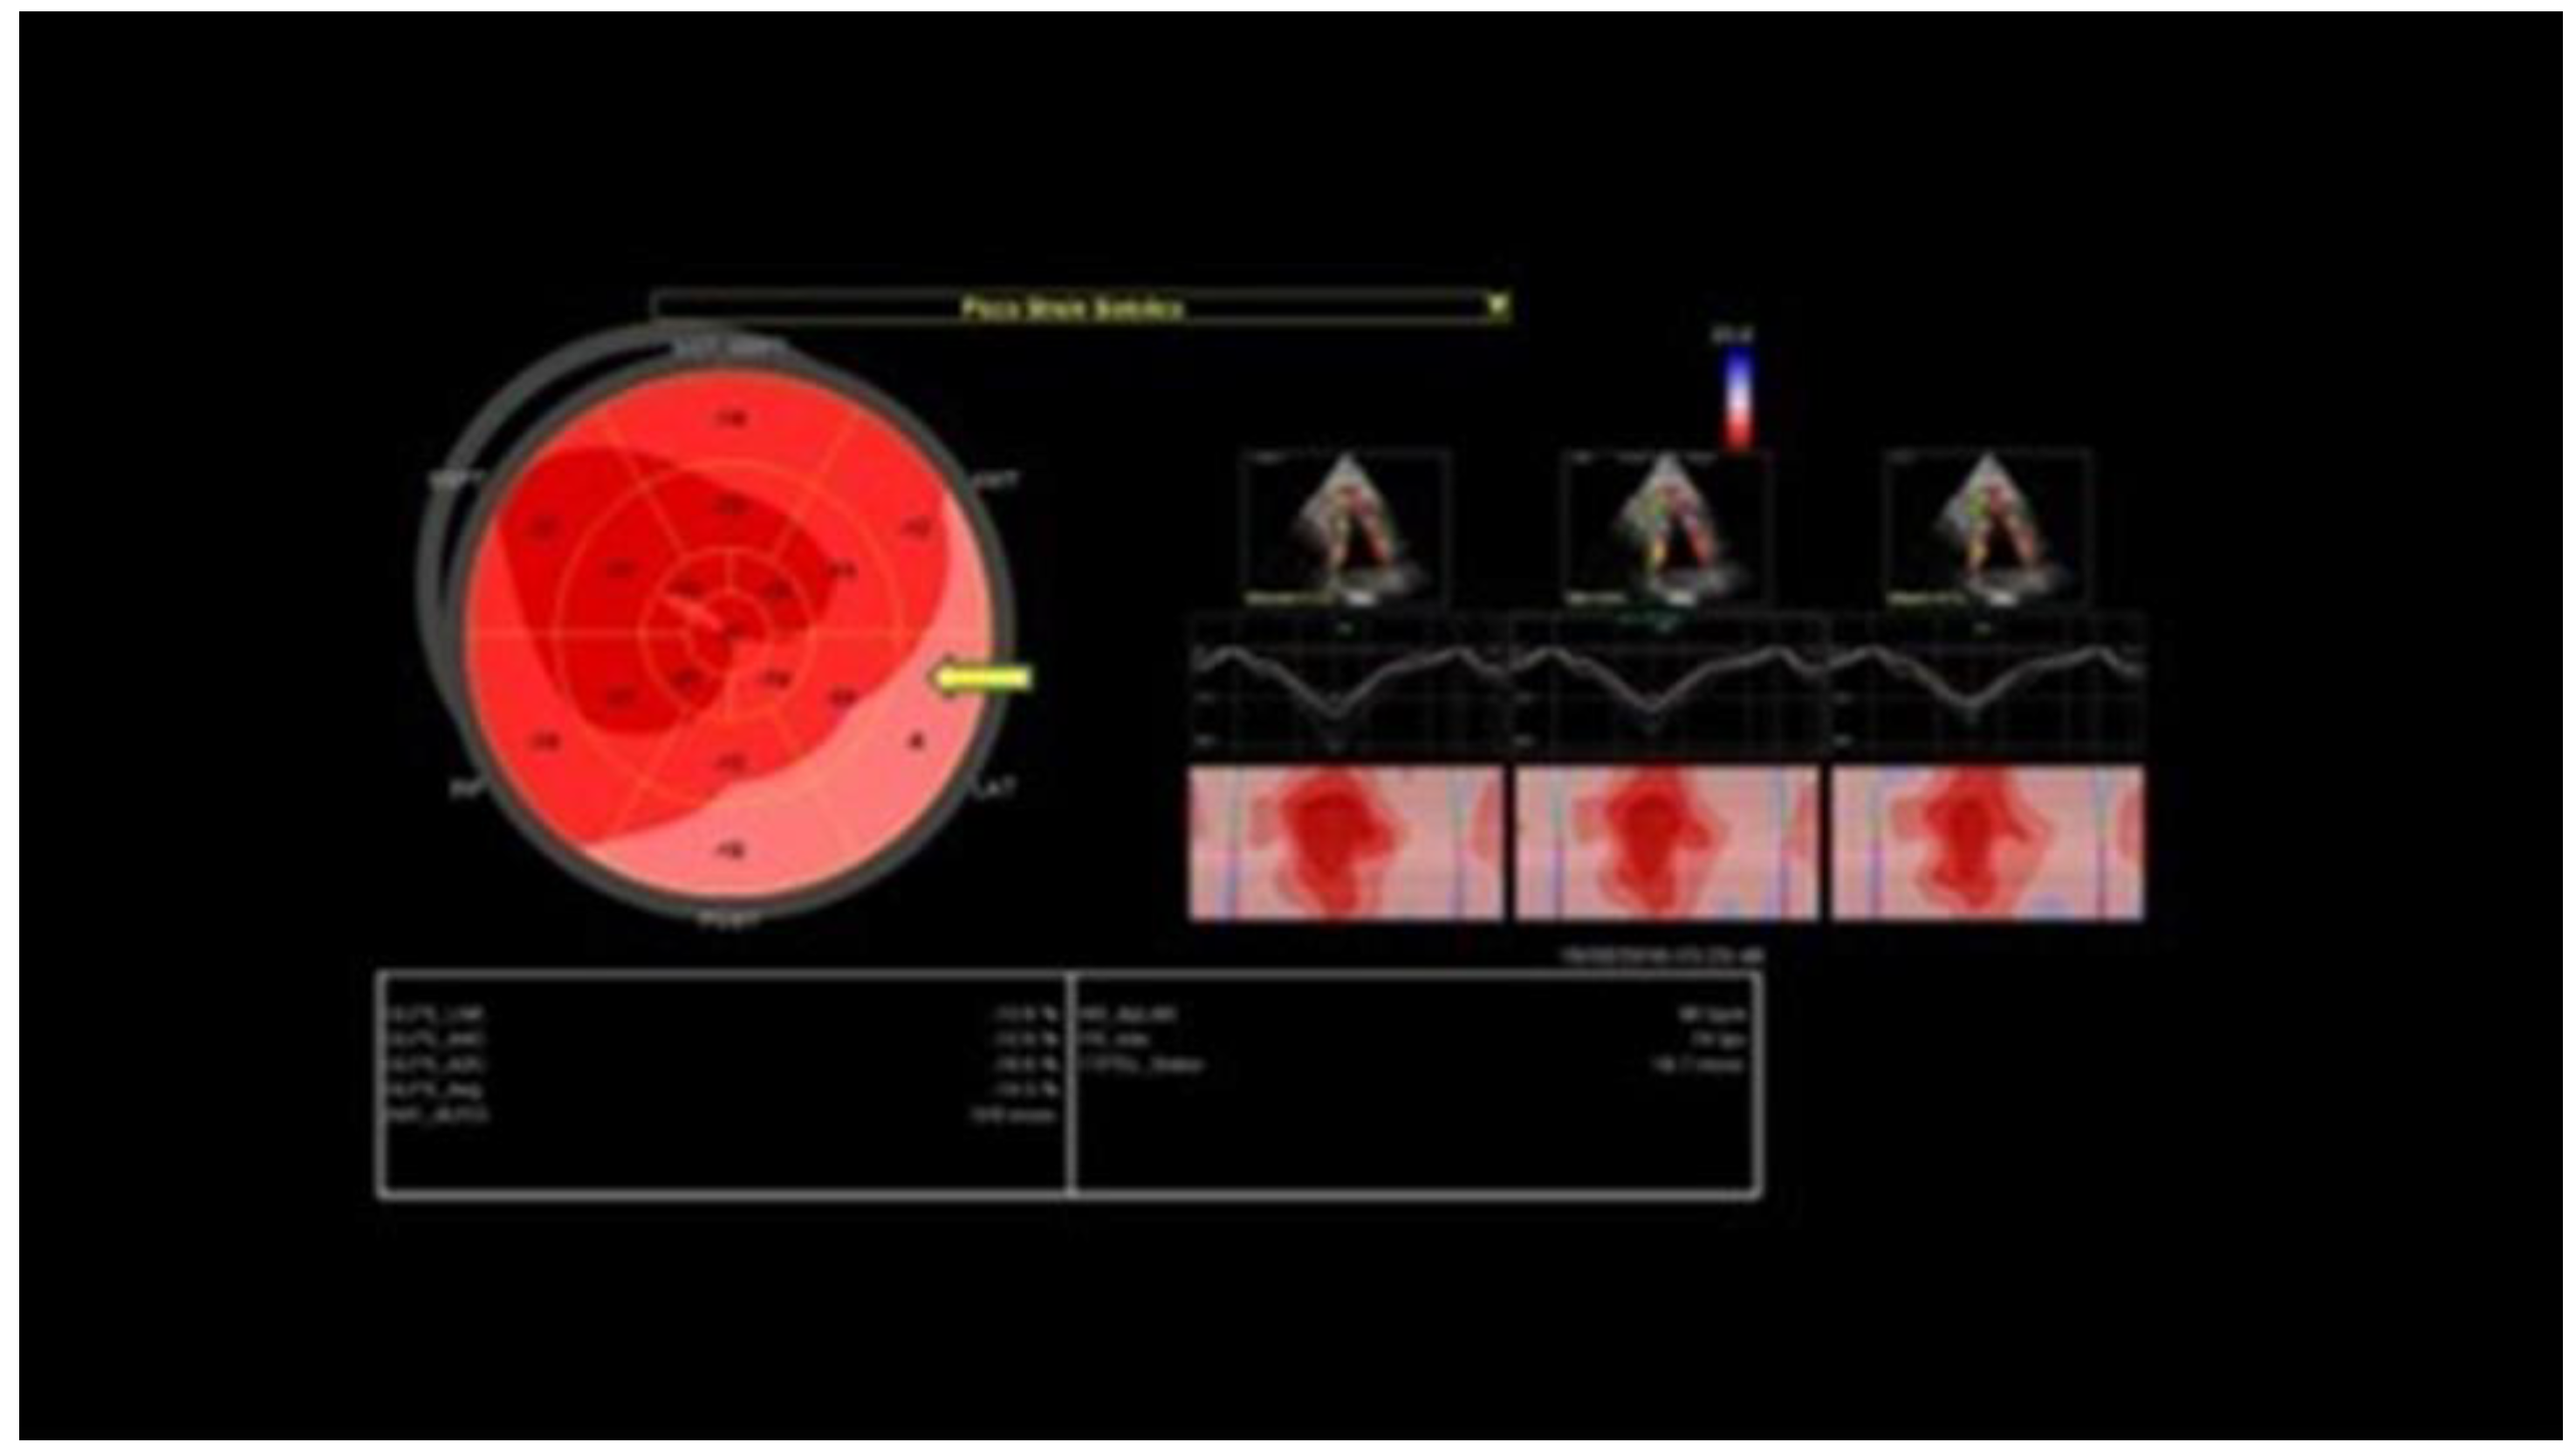

- Tweet, M.S.; Pellikka, P.; Oh, J.; Hayes, S. Echocardiographic findings in acute spontaneous coronary artery dissection. J. Am. Coll. Cardiol. 2021, 77, 220. [Google Scholar] [CrossRef]